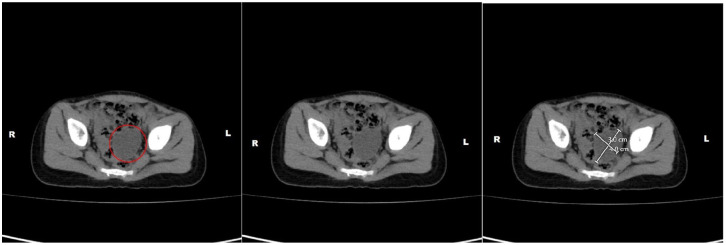

麦昆-奥尔布赖特综合征(mcune - albright syndrome, MAS)是一种罕见的疾病,发病率为10万分之一至100万分之一,由GNAS基因的受精卵后体细胞突变引起。这导致纤维发育不良(FD),卡萨芬-au-lait (CAL)皮肤色素沉着和功能亢进的内分泌病。我们报告一个32个月大的女孩,阴道反复出血,双侧乳房增大,并有多个不规则的CAL斑点穿过中线。影像学显示卵巢囊肿和骨骼病变符合FD。实验室结果显示性腺激素不依赖型性早熟。临床诊断为MAS,基因检测被认为是不必要的。MAS表现出不同的严重程度,早期诊断需要临床识别其标志性特征。基因检测可以支持诊断,尽管其可靠性可能因镶嵌现象而有所不同。治疗是对症的,重点是控制内分泌功能障碍和减少骨骼并发症。新兴疗法提供了希望,但没有绝对的治愈方法。早期识别和管理对于优化结果至关重要。

McCune-Albright syndrome (MAS) is a rare disorder, occurring in 1 in 100 000 to 1 in 1 000 000 live births, caused by post-zygotic somatic mutations in the GNAS gene. This leads to fibrous dysplasia (FD), café-au-lait (CAL) skin pigmentation, and hyperfunctioning endocrinopathies. We present a 32-month-old girl with recurrent vaginal bleeding, bilateral breast enlargement, and multiple irregular CAL spots crossing the midline. Imaging revealed ovarian cysts and skeletal lesions consistent with FD. Laboratory findings indicated gonadotropin-independent precocious puberty. A clinical diagnosis of MAS was made, and genetic testing was deemed unnecessary. MAS presents with variable severity, and early diagnosis requires clinical recognition of its hallmark features. Genetic testing can support the diagnosis, though its reliability may vary due to mosaicism. Management is symptomatic, focusing on controlling endocrine dysfunction and minimizing skeletal complications. Emerging therapies offer promise, but no definitive cure exists. Early recognition and management are crucial for optimizing outcomes.